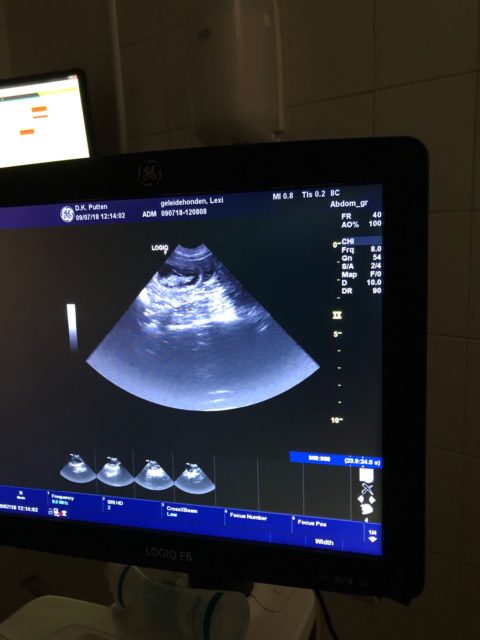

lexi is drachtig van Benz!!

Op 9 en 10 juni is Lexi gedekt door Benz

hopelijk is zij drachtig en kunnen wij weer mooie pups bij gastgezinnen plaatsen.!